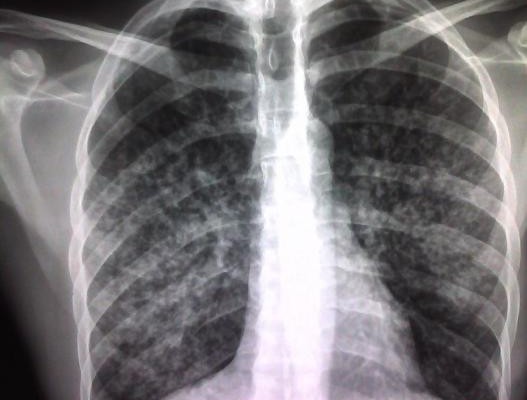

Además, han recordado que Madrid Salud tiene un programa de prevención y control de tuberculosis, una enfermedad contagiosa (se transmite a través del aire) causada por una bacteria y que casi siempre afecta a los pulmones.

Este organismo municipal se encarga de hacer una captación activa de posibles casos de tuberculosis entre los grupos de la población con peor acceso sanitario, para lo que utiliza un vehículo dotado con radiología.